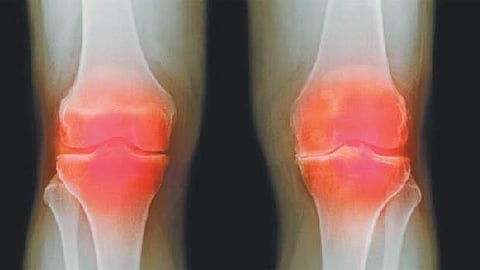

மூட்டுப் பகுதியில் எலும்புகளுக்கிடையிலான உராய்வு ஏற்படாமலிருக்கவும், "சிலேஷகம்' என்ற ஒரு கபம் அவ்விடத்தில் வழுவழுப்பை ஏற்படுத்தி, பாதுகாப்பான அரணாக விளங்குகிறது. வயோதிகத்தில், உணவினுடைய செரிமான விசேஷத்தினால் இப்பகுதிக்கு வர வேண்டிய ஊட்டச் சத்தான குணங்களாகிய நெய்ப்பு, கனம், மந்தம், வழவழப்பு போன்றவை வராமல் போவதால் தான்... இந்த சிலேஷகம் என்ற கபம் தன் செயல்திறன் குன்றி, வாயுவினுடைய குணங்களாகிய வறட்சி, லேசு, குளிர்ச்சி, சொர சொரப்பு ஆகியவற்றிற்கு வழி விடுவதால், மூட்டுத் தேய்மானம் ஏற்படுகிறது.

மேற்குறிப்பிட்ட ஊட்டச் சத்தான குணங்களை, பாசகம் எனும் உணவைச் சீராக செரிமானம் செய்யும் பித்தத்தை, வயோதிகத்தில் மனிதர்கள் பொதுவாக இழப்பதால், நாம் என்னதான் சாப்பிட நேர்ந்தாலும், சீரான செரிமானம் சரிவர ஏற்படாததால், அவை கழிவுகளாக மாறி, மலம் , சிறுநீர், வியர்வை போன்றவற்றின் வழியாக வெளியேறுகின்றன. அதனால், மூட்டுத் தேய்மானம் ஏற்படும் நிலையில், பலரது சிந்தனையும் மூட்டுப் பகுதியை நோக்கியே குவிகிறது என்பதாலும், செரிமான விசேஷத்திற்கு அத்தனை முக்கியத்துவம் கொடுக்காமல் போவதாலும், மூட்டுத் தேய்மானம் என்பதை நிரந்தரமாக குணப்படுத்த இயலாமல் போகிறது.